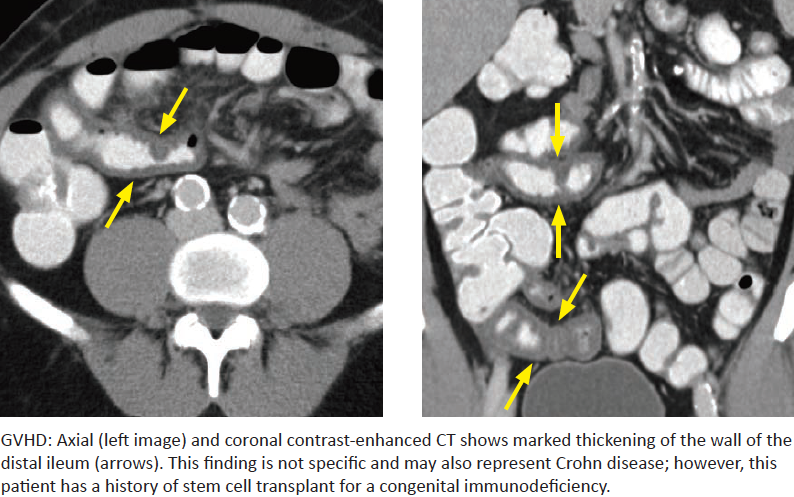

Graft Versus Host Disease

What is it? What organ systems are most commonly affected?

Image findings? What is the classic barium finding and how often is it seen?